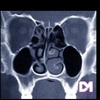

4